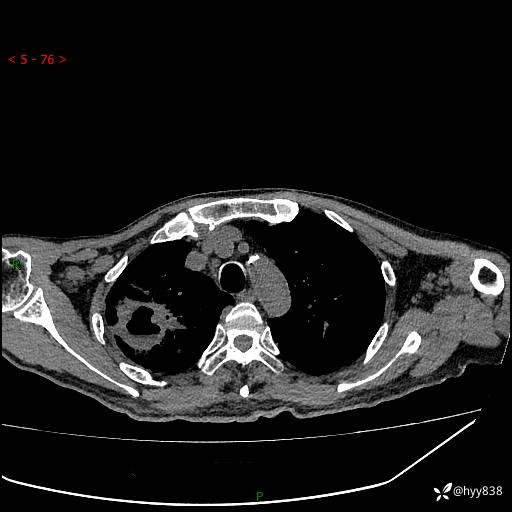

第一次胸部CT检查